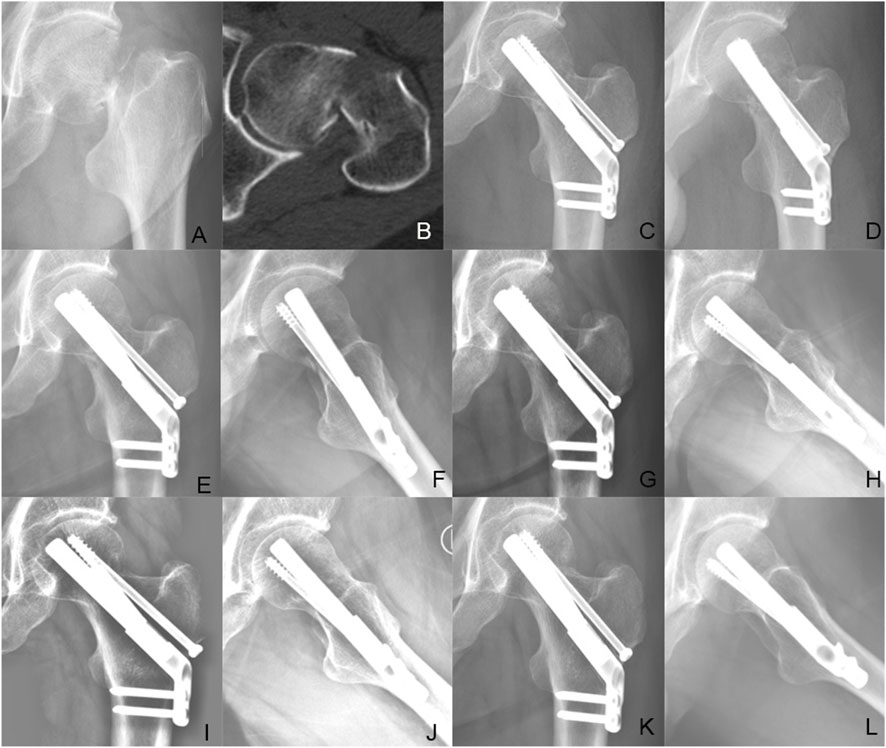

Background The purpose of this study was to explore the biomechanical property and clinical efficacy of femoral neck system (FNS) with an additional cannulated screws (CS) in the treatment of unstable femoral neck fracture (FNFs) with comminuted posteromedial cortex. Methods Firstly, we developed a model of Pauwels type III FNF with comminuted posteromedial cortex for the finite element analysis (FEA). Two experimental models were set up: the FNS model and the FNS+CS model. The von Mises stress on the proximal femur, implant and the total displacement of the device components were evaluated for both FNS and FNS+CS models. Secondly, we retrospectively included the cases of vertical FNFs with comminuted posteromedial cortex by FNS or FNS+CS fixation in our hospital from January 2020 to December 2023. In this study, demographic information, femoral neck shortening, Harris score of hip joint function, and postoperative complications were collected and compared. Results The FEA results showed similar peak von Mises stress of the implant in two models and the additional CS could share the stress concentration with the FNS in the FNS+CS model. In terms of proximal femur, the maximum von Mises stress of the FNS model increased by 15.43% when compared with the FNS+CS model, and the magnitude of these two models were 83.02MPa and 71.92 MPa, respectively. Furthermore, the maximum displacement in the FNS+CS model was much smaller than that in the FNS model. Clinically, the femoral neck shortening distance was significantly longer in the FNS group (5.62±3.32 mm) than that in the FNS+CS group (3.49±2.01 mm) (p = 0.027). Furthermore, the incidence of moderate to severe shortening (≥ 5 mm) was significantly higher in the FNS group compared with the FNS+CS group (p = 0.039). Moreover, the patients in the FNS+CS group had a higher Harris score than patients in the FNS group (91.97 vs. 88.56, p = 0.003). Conclusions Compared to the FNS alone, the FEA results showed that the FNS+CS had better biomechanical properties and the clinical results showed that the FNS+CS had a shorter femoral neck shortening and higher Harris score in treating unstable FNFs with comminuted posteromedial cortex.